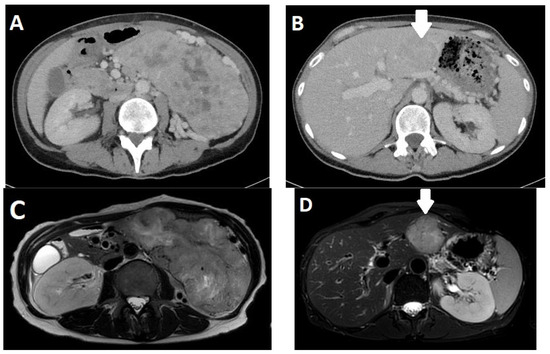

3.4. Imaging

- Kim, J.H.; Eun, H.W.; Kim, Y.J.; Lee, J.M.; Han, J.K.; Choi, B.I. Pancreatic neuroendocrine tumour (PNET): Staging accuracy of MDCT and its diagnostic performance for the differentiation of PNET with uncommon CT findings from pancreatic adenocarcinoma. Eur. Radiol. 2016, 26, 1338–1347. [Google Scholar] [CrossRef] [PubMed]

- Gallotti, A.; Johnston, R.P.; Bonaffini, P.A.; Ingkakul, T.; Deshpande, V.; Fernandez-del Castillo, C.; Sahani, D.V. Incidental neuroendocrine tumors of the pancreas: MDCT findings and features of malignancy. AJR Am. J. Roentgenol. 2013, 200, 355–362. [Google Scholar] [CrossRef] [PubMed]

- Owen, N.J.; Sohaib, S.A.; Peppercorn, P.D.; Monson, J.P.; Grossman, A.B.; Besser, G.M.; Reznek, R.H. MRI of pancreatic neuroendocrine tumours. Br. J. Radiol. 2001, 74, 968–973. [Google Scholar] [CrossRef]

- Bicci, E.; Cozzi, D.; Ferrari, R.; Grazzini, G.; Pradella, S.; Miele, V. Pancreatic neuroendocrine tumours: Spectrum of imaging findings. Gland. Surg. 2020, 9, 2215–2224. [Google Scholar] [CrossRef]

- d’Assignies, G.; Fina, P.; Bruno, O.; Vullierme, M.P.; Tubach, F.; Paradis, V.; Sauvanet, A.; Ruszniewski, P.; Vilgrain, V. High sensitivity of diffusion-weighted MR imaging for the detection of liver metastases from neuroendocrine tumors: Comparison with T2-weighted and dynamic gadolinium-enhanced MR imaging. Radiology 2013, 268, 390–399. [Google Scholar] [CrossRef]